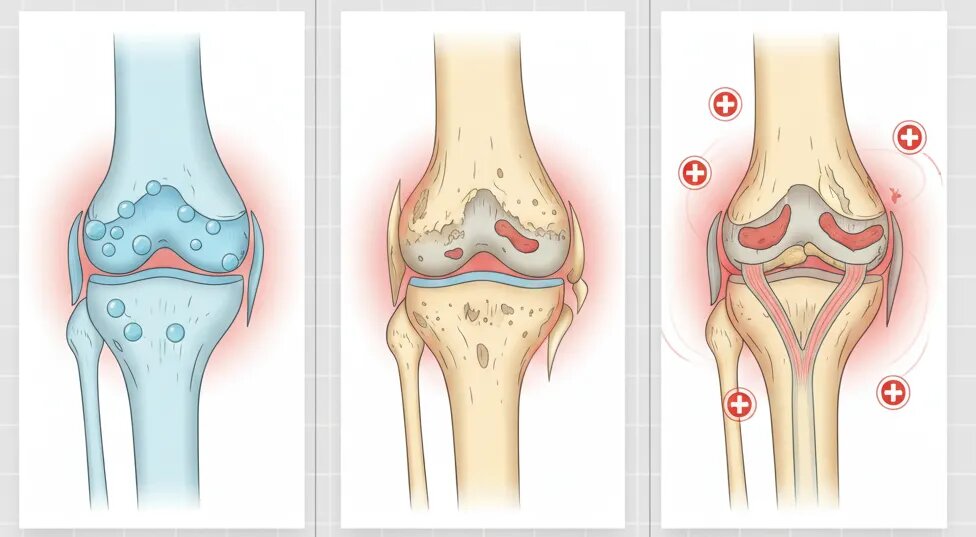

Хруст может быть результатом нормальных биомеханических процессов, таких как образование пузырьков газа в синовиальной жидкости или скольжение сухожилий по костным выступам. Этот процесс чаще всего не сопровождается болью и не требует лечения.

Остеоартрит

Остеоартрит является наиболее распространённой причиной хруста в коленях, особенно у пожилых людей. Состояние характеризуется дегенерацией хряща и изменениями в структуре сустава, что может приводить к трению костей и хрусту.

Травмы и дегенеративные изменения

Повреждения менисков, хрящей или связок также могут вызывать хруст, особенно при движении колена. В таких случаях хруст часто сопровождается болью, отёками и ограничением подвижности.